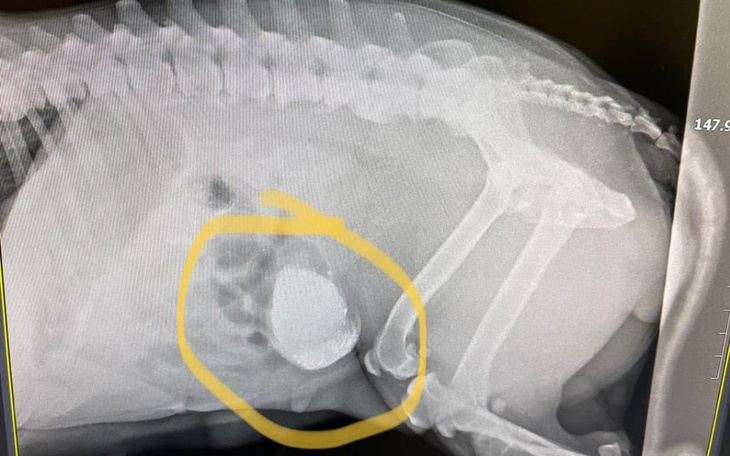

Maleńka znalezionab w niedziele stafiorka trafiła dziś na przegląd weterynaryjny. I niestety została w klinice. Lekarzy zaniepokoił wygląd brzucha, zarządzono USG , a tu taka niespodzianka. Sunia po porodzie pozostawione łożysko, a w nim prawdopodonie martywy płód. Macica zmieniona zapalnie, pojawił się już płyn w jamie brzusznej. Dostała na szybko kroplówkę i czeka na zabieg . Trzymajcie kciuki bo nie jest dobrze. Jak wcześniej wspominaliśmy sunia to nasz już ponadstan więc dodatkowe koszty to smutna rzeczywistość . Pomożecie?